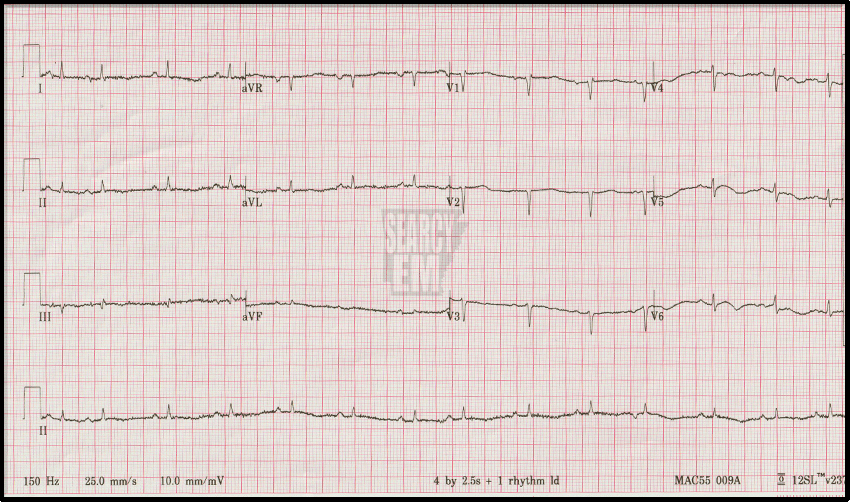

A typical day of EKGs EKG 1: interpretation EKG 2: interpretation EKG 3: interpretation EKG 4: interpretation EKG 5: interpretation EKG 6: interpretation EKG 7: interpretation EKG 8: interpretation EKG 9: interpretation EKG 10: interpretation EKG 11: interpretation EKG 12: interpretation EKG 13: interpretation EKG 14: interpretation EKG 15: interpretation EKG 16: interpretation EKG 17: interpretation EKG 18: interpretation EKG 19: interpretation EKG 20: interpretation EKG 21: interpretation EKG 22: interpretation EKG 23: interpretation Share this: Share on X (Opens in new window) X Share on Facebook (Opens in new window) Facebook Like Loading...